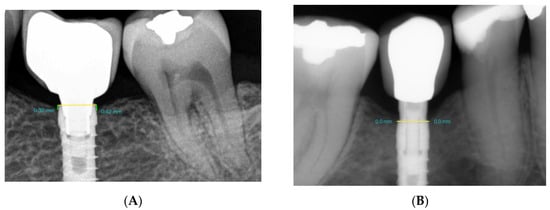

2.3. Sample Randomization

2.6. Radiological Marginal Bone Level Evaluation

3.2. Bone Levels